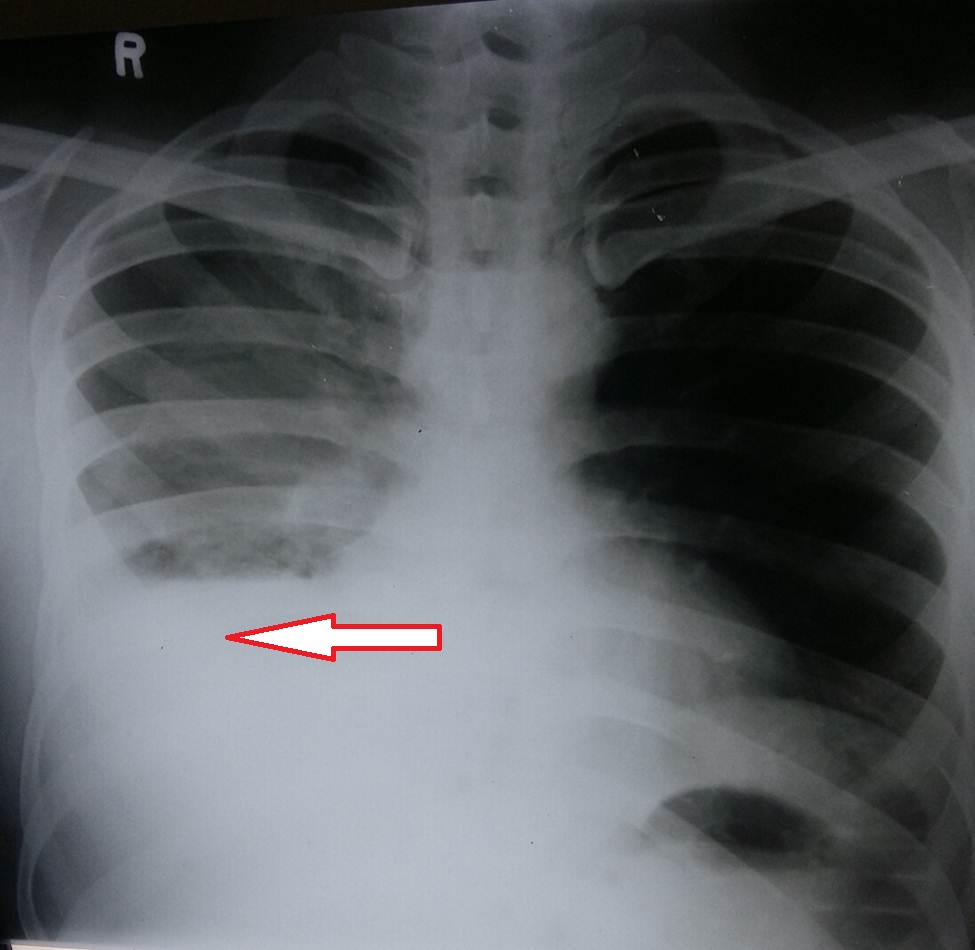

- Figure 1 - Right sided pleural effusion

- Figure 2 - Right sided hemothorax